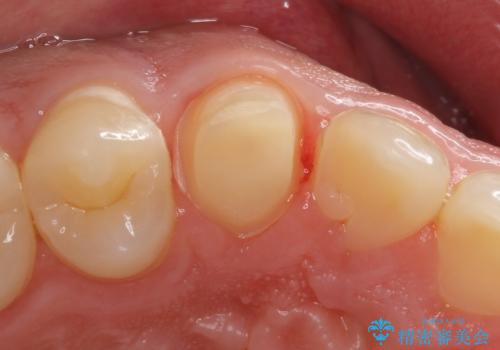

インレーでの修復はできない場所であるため、セラミッククラウンでの治療になりました。

- 右上3 e-maxクラウン 77000円×1本費用は治療当時の料金となります

全体的に歯の脱灰が目立っており、右上の犬歯のみ状態が悪く穴が開いてしまっていました。

審美的にも優れるセラミッククラウンで修復し、他の歯も同じ状態になってしまわないよう歯磨き指導をさせていただきました。